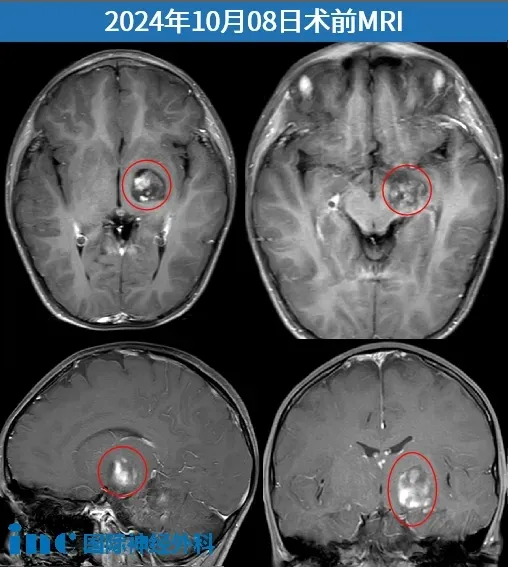

術(shù)前影像